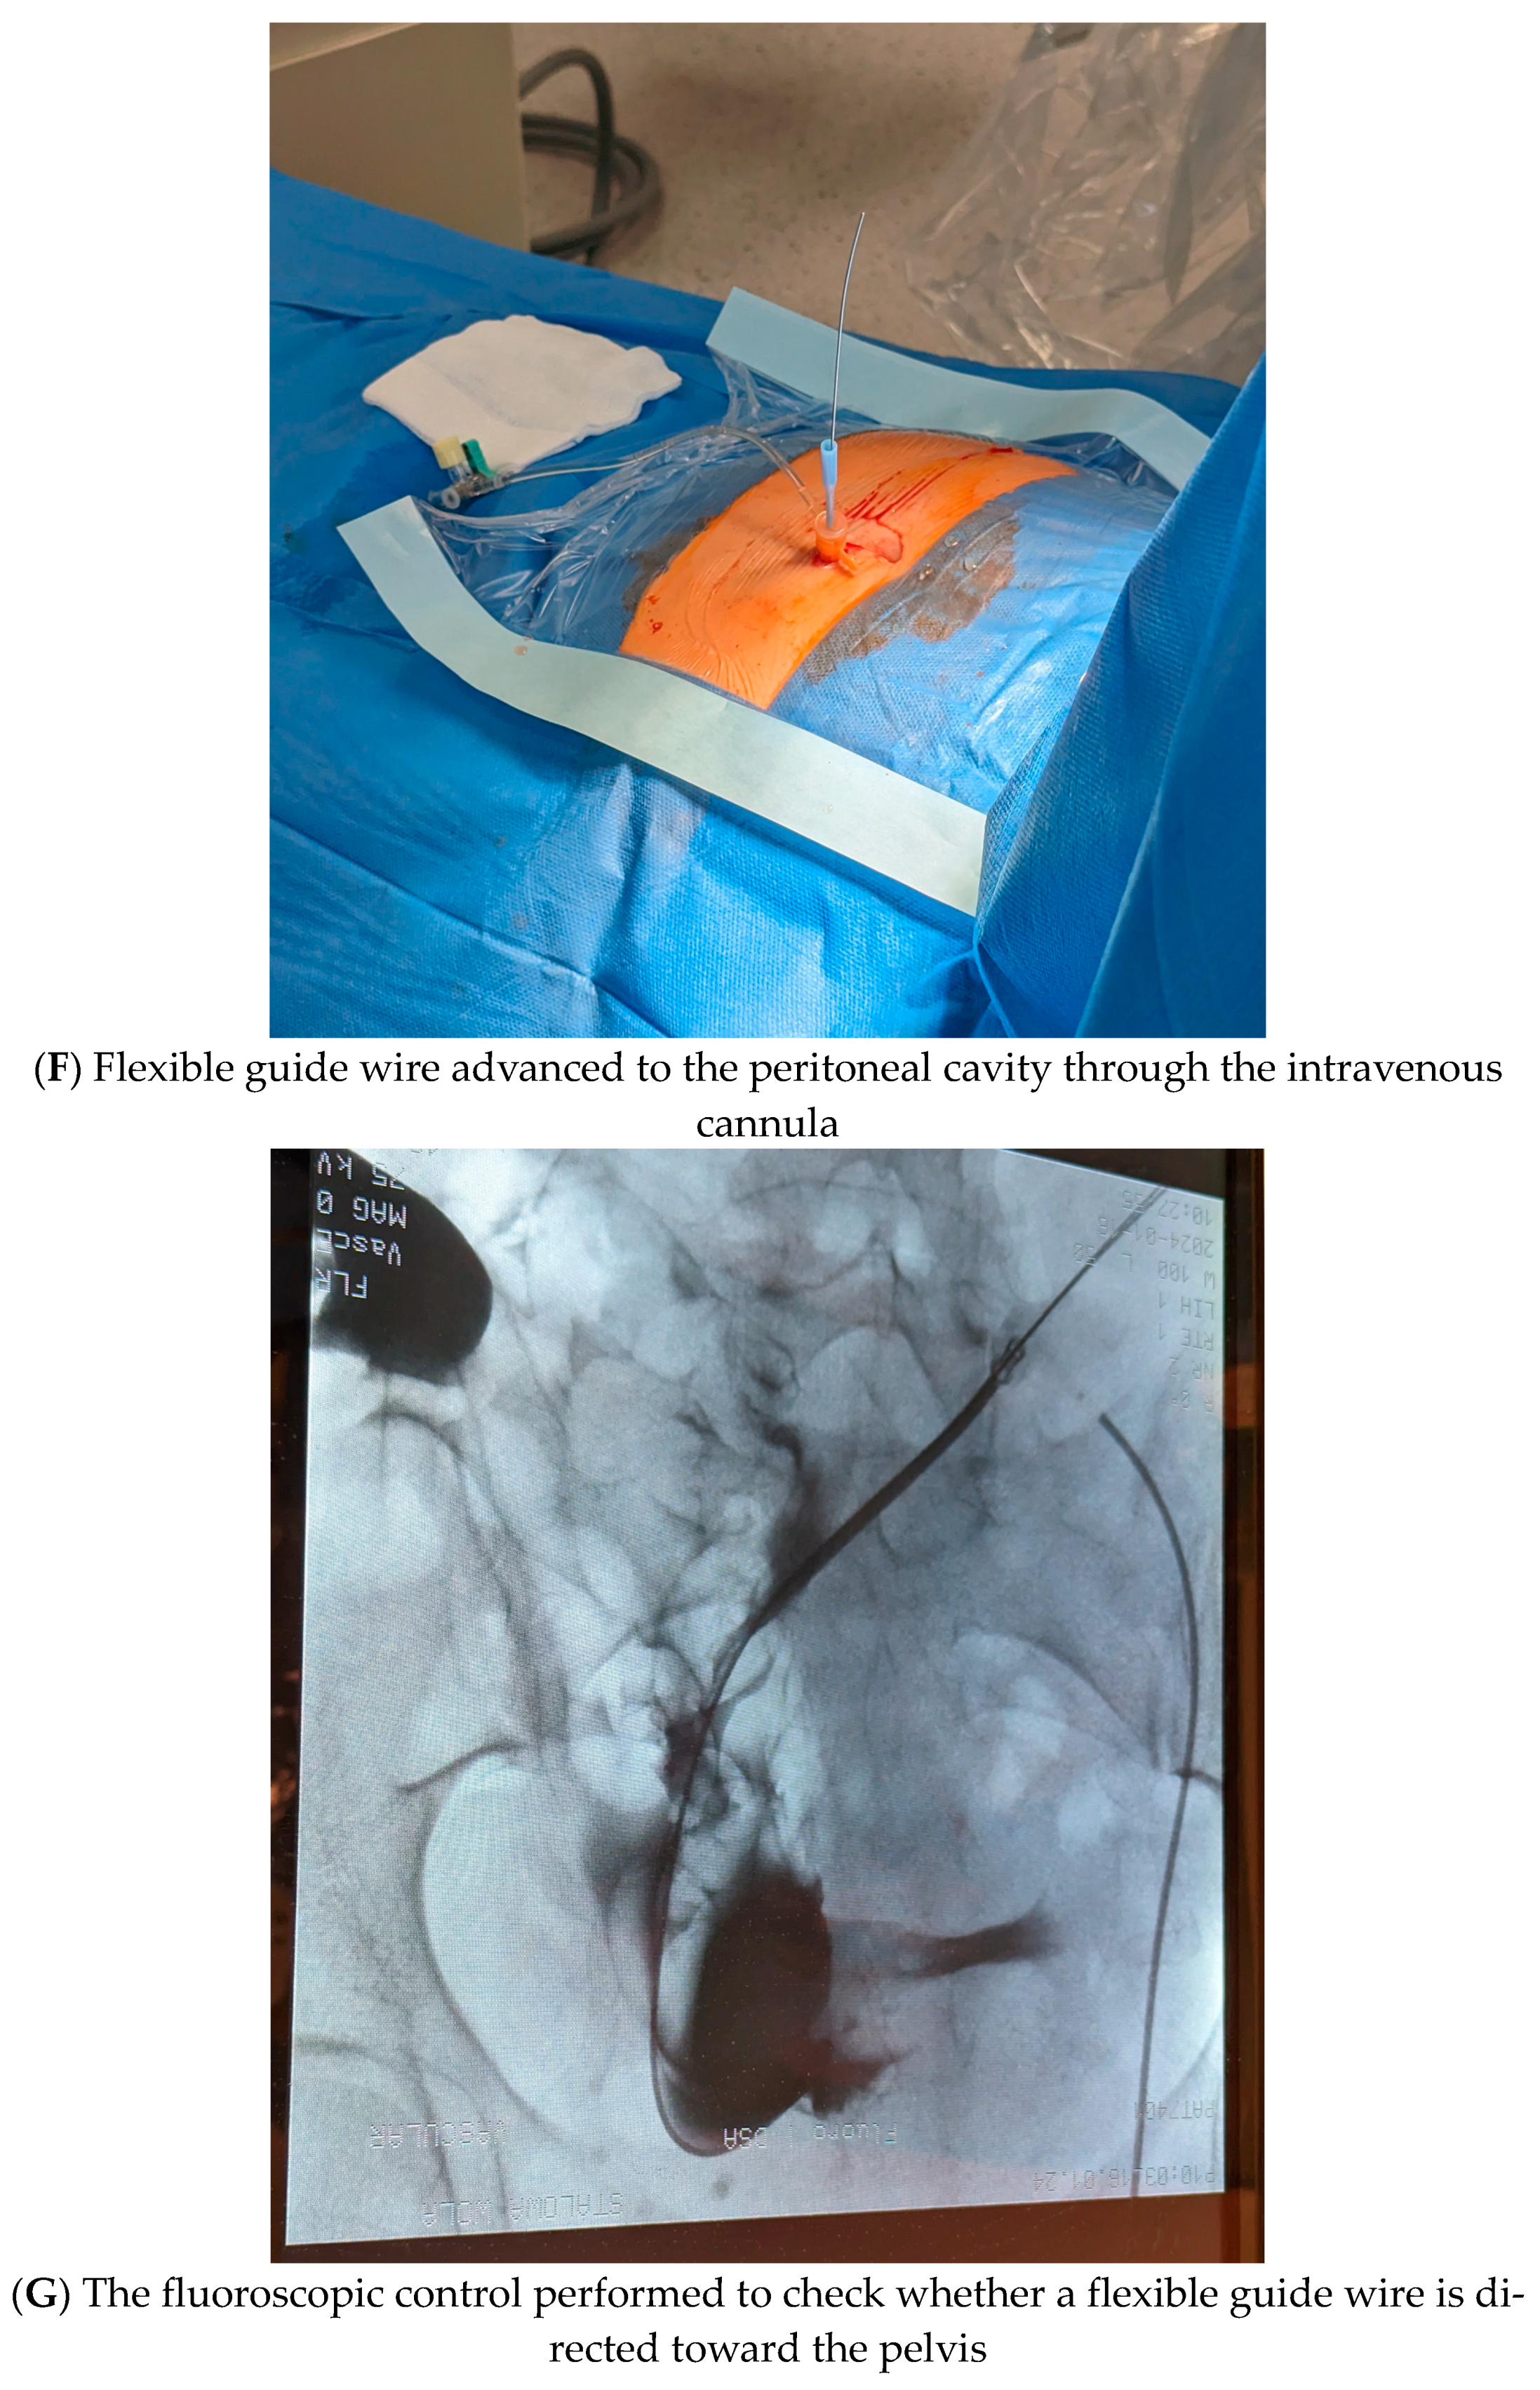

- (5)

- Once peritoneal cavity access was achieved, a flexible guide wire was advanced through the intravenous cannula (Figure 1F). Next, the fluoroscopic control was performed to check whether a flexible guide wire was directed toward the pelvis (Figure 1G). If yes, the intravenous catheter was replaced, and a dilator and the peel-away sheath (Argyle–Peritoneal Dialysis Catheter Kit, Covidien, Mansfield, MA, USA) were advanced over the wire into the abdominal cavity (Figure 1H). Next, a guide wire as well as the introducer of the peel-away sheath were removed, leaving the tubing in the abdomen.